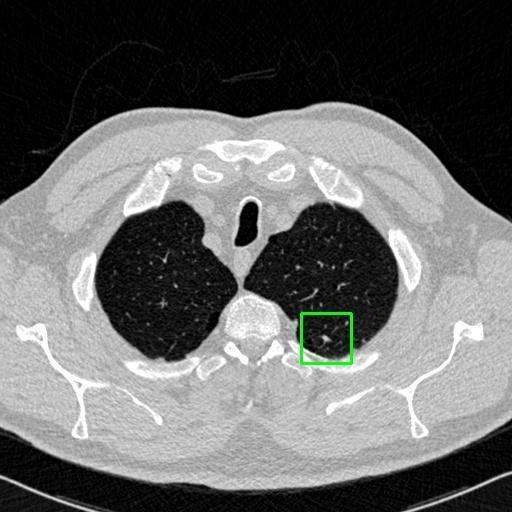

We developed an AI-based system using deep learning models for analyzing lung CT scans to detect and classify pulmonary nodules. We chose the YOLOv11 architecture for its enhanced object detection capability and adapted it specifically for medical imaging, incorporating pixel-level precision and severity classification.

Classification into three severity levels with colored bounding boxes.

Designed a severity classification system that categorizes nodules into null, moderate, and severe using colored bounding boxes, assisting in rapid clinical decision-making.